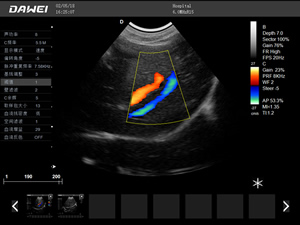

·支持彩色多普勒、頻譜多普勒、能量多普勒、連續多普勒等成像技術